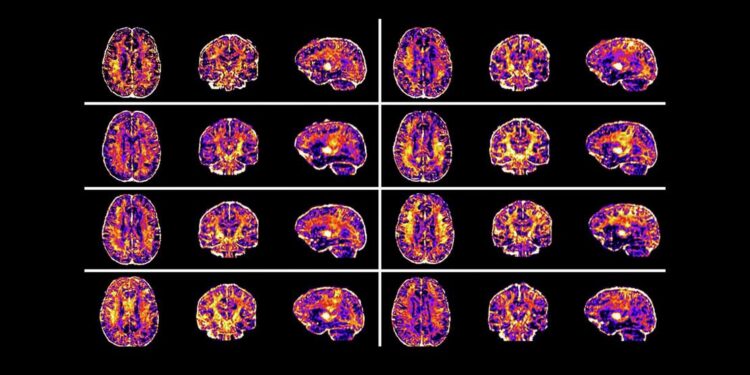

Analizaron las resonancias magnéticas para estudiar el área superficial y el grosor de las regiones en la corteza, incluidas las involucradas en funciones cognitivas superiores como la memoria, la atención, la emoción y el lenguaje.

También examinaron las conexiones entre diferentes regiones del cerebro utilizando resonancias magnéticas, donde los cambios en el flujo sanguíneo indican la actividad cerebral.

*Resonancias de más niños estadounidenses confirman que las brechas sociales afectan al neurodesarrollo y elevan el riesgo de depresión y ansiedad en la niñez y la adolescencia | Nature Mental Health

Los escáneres mostraron que los niños que viven en áreas con mayores niveles de desigualdad social están asociados con una superficie reducida de la corteza y conexiones alteradas entre múltiples regiones del cerebro.

Estos hallazgos proporcionan evidencia de un neurodesarrollo afectado, que podría relacionarse con la salud mental y la función cognitiva futuras, defienden los autores.